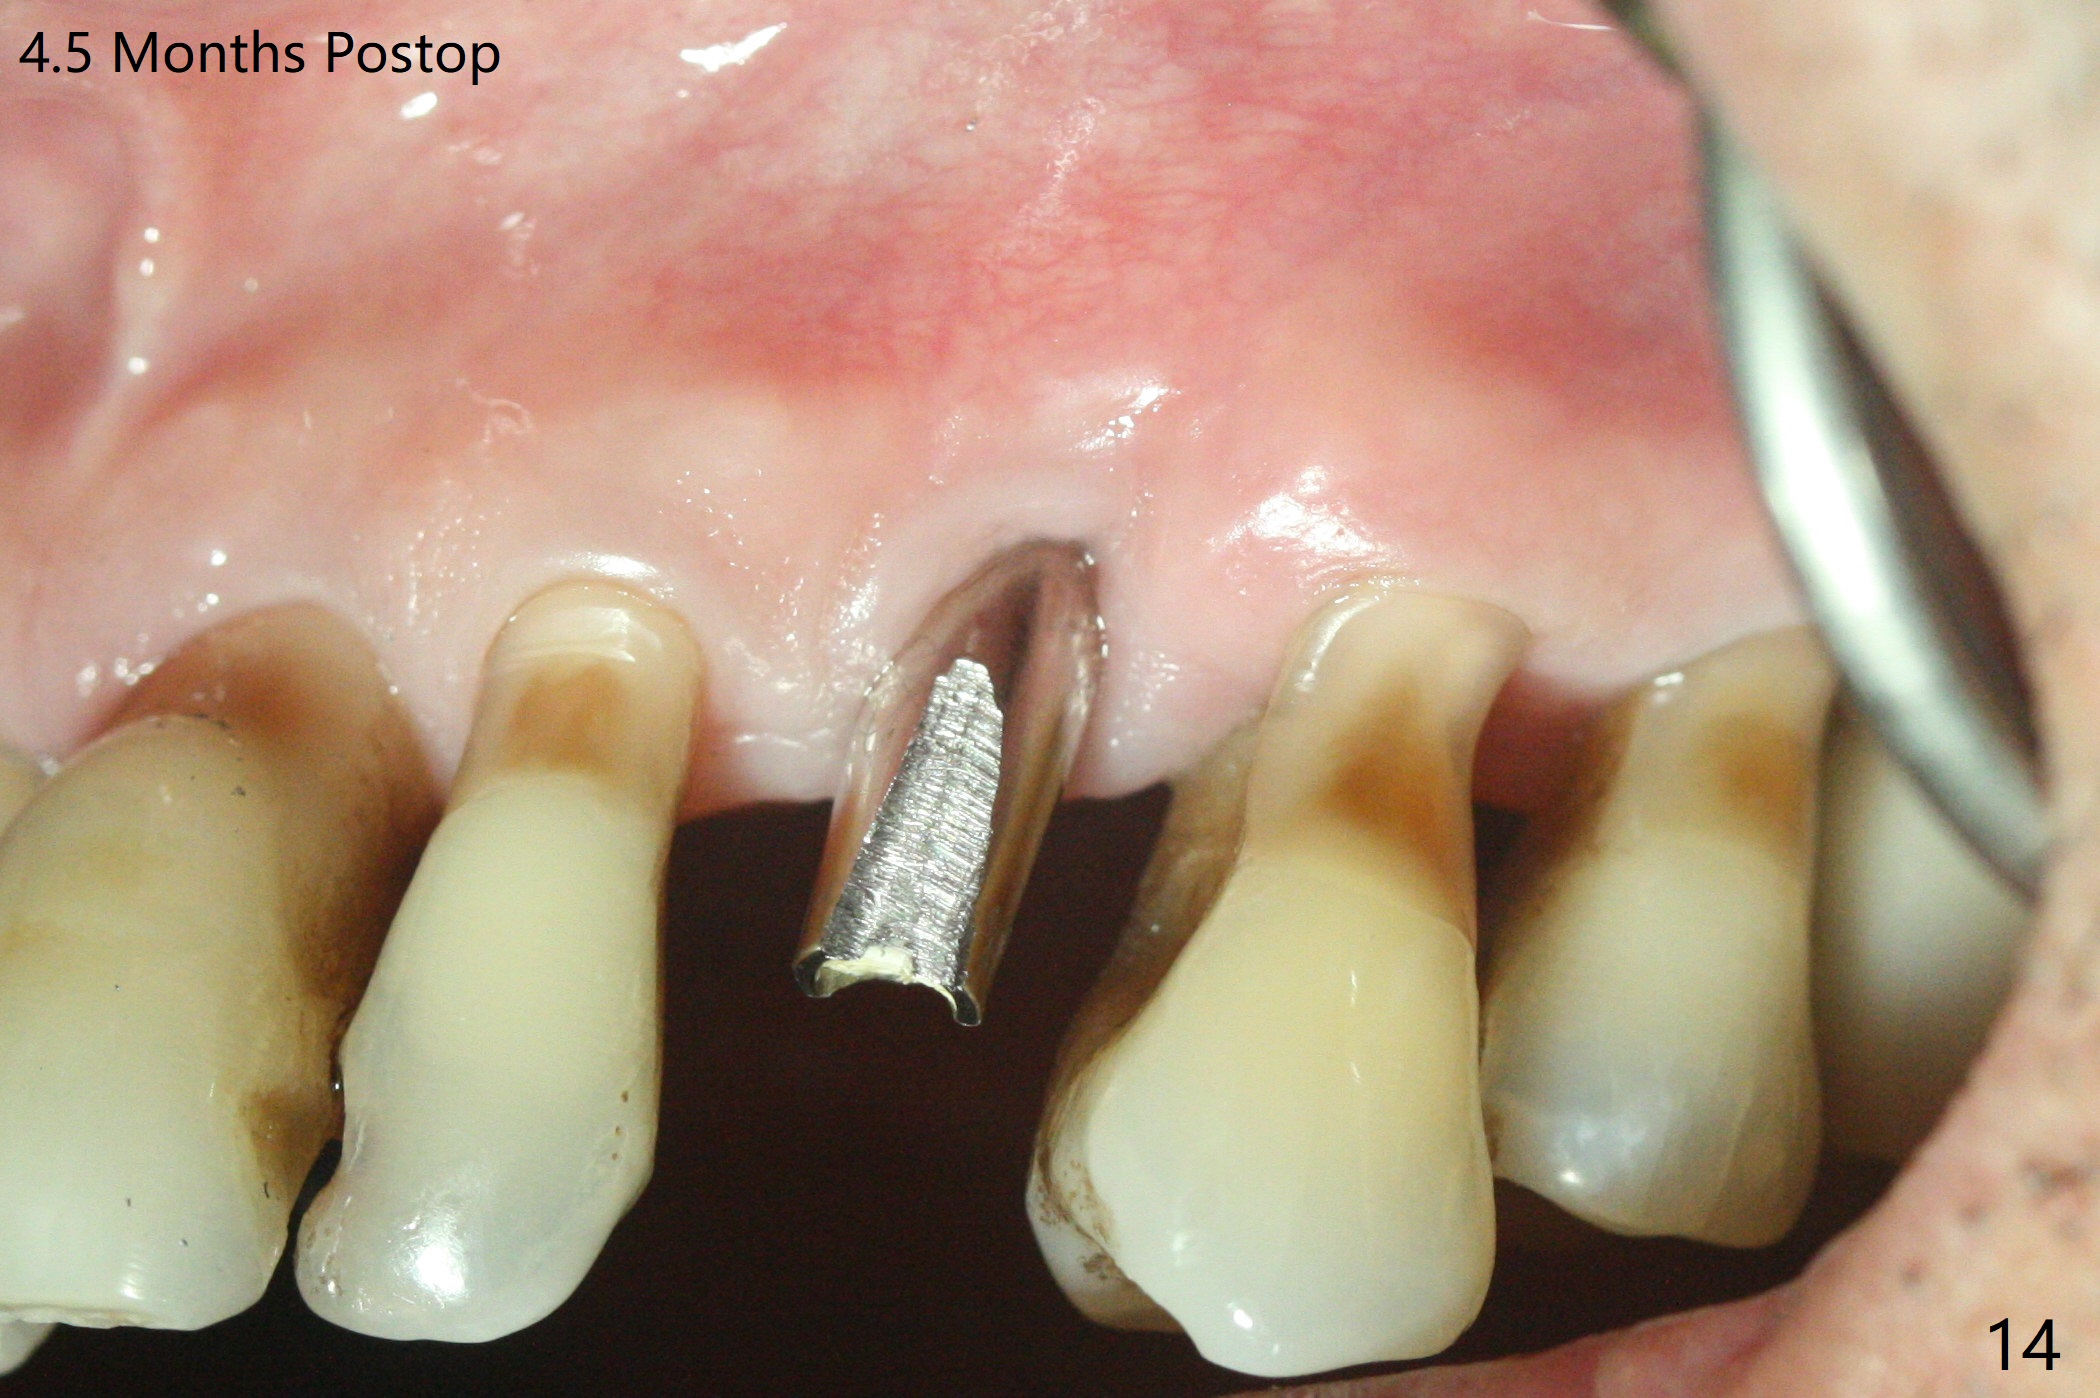

A 62-year-old man with generalized chronic periodontitis returns with chief complaint of loose tooth at #11 (Fig.1). Although a buccal fistula (Fig.1 <) is closer to #12 than to #11, percussion is more severe at #11 than 12. The buccal plate of #11 is missing, but it is possible to place a narrow immediate implant because of the wide alveolus (Fig.2). Since the gingiva is ~ 10 mm long, a mill abutment is to be used (Fig.3,5). In fact the fistula communicates with #11 extraction socket. After debridement, osteotomy is initiated (Fig.4) for a 3.8x10 mm implant ~ 35 Ncm, followed by seating a 4.5x2 mm mill abutment (Fig.5). Abundant sticky bone is placed in the remaining socket (for buccal plate reconstruction) and against the root surface of the neighboring teeth (Fig. 6 * (#10,12)). Finally 2 pieces of PRF membranes are utilized to facilitate repair of the buccal soft tissue defect (Fig.7 *). The root prominence of the canine seems to be maintained by the bone graft (Fig.8 C). Acrylic dressing holding the PRF membranes in place remains in situ with the healthy gingiva buccal (Fig.9) and palatal (Fig.10) 11 days postop. Note the acrylic locking into the undercuts of the neighboring teeth (*). 经过一段摸索发现离心每分钟1500转5分钟后,抽取上清液,接着再离心10分钟剩余上清液就形成血小板块,压制后便是血小板膜,后者似乎有助于软组织愈合,而上清液用来制备骨块,帮助硬组织生长。利用这个原则讨论以下病例治疗。The gingival margin gains ~ 5 mm 6 weeks postop when the acrylic dressing is removed (Fig.11,12 (<: previous one), as compared to Fig.7,8). 治疗结束时尖牙牙龈缘高于第一双尖牙(图七,八),六个星期后,尖牙牙龈缘却低于双尖牙(图十一,十二(箭头:原始牙龈缘))。术后2.5,4.5月基台周围牙龈似乎能与钛合金附着,防止细菌进入深部植体(图十三,十四)。临时牙冠脱落多次,可能与mill abutment太光滑有关,所以颊侧,舌侧磨成平面(图十四)。取模时好像不必取出基台清洗(仿佛没有炎症),原位用树脂延长基台。术后5个月CT显示颊侧骨板再生(图十六-十八)。取模时并没有用树脂加长基台;粘固时,牙冠颜色理想,但是照片中并不是如此(图十九,二十),颊侧骨板没有塌陷。术后11个月基台颊侧骨板没有萎缩(图二十一:B);3d图像:骨壁完全形成(图十六对比:部分形成)。密度也增高(图二十二:B),与术后五个月比较(图十七)。术后十一个月,粘固后五个月角化龈存在(图二十三),牙冠颈部有金属颜色透出,是因为二段式基台太粗了(最细4.5毫米),可以请实验室在牙冠内部涂opaque material而减轻。